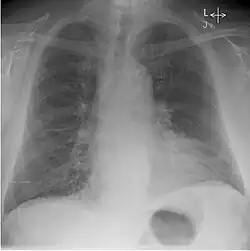

Whilst working at Westminster and the Royal Chest Hospital, Kerley published on the X-ray features of early Pulmonary tuberculosis. As well as his 'B lines' in congestive heart failure he also reviewed X-ray changes in congenital lung diseases, congenital heart disease, intrathoracic aneurysm and bronchiectasis. He gave one of the earliest accounts of chest X-ray and contrast, that is bronchography and lipiodol.[3]

He discovered several of the medical signs used in interpreting radiographs. Famous for his 'B' lines, Kerley B lines are a finding of congestive heart failure.[3] These are short parallel lines perpendicular to the lateral lung surface, indicative of increased opacity in the pulmonary septa. Kerley A lines and Kerley C lines are related findings.[1]